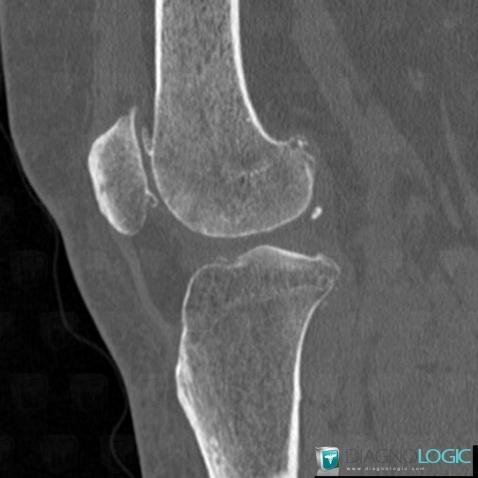

Ostéochondromatose synoviale, Articulations fémoro tibiales / Echancrure, Scanner

Voici les informations spécifiques à l'image clé ci dessus:

- Diagnostic Ostéochondromatose synoviale, Localisation(s) Articulations fémoro tibiales / Echancrure, comportant les gammes Calcification intra ou périarticulaire, Masse des parties molles juxta articulaires, Arthropathie avec nodules des parties molles